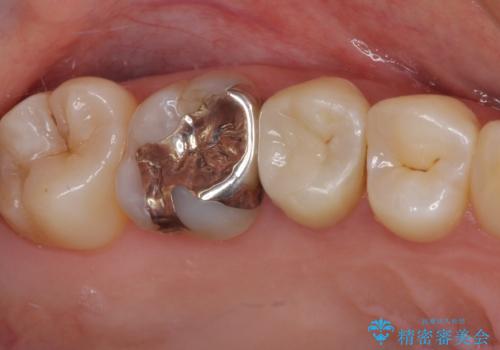

- 冷たいものがしみるとのことで来院された患者様です。

レントゲン写真より、第一小臼歯にやや大きい虫歯があることが分かりました。

症状などから診断したところ、神経を取る可能性は低いと考えられたため、セラミックインレーによる修復治療を行うこととしました。

奥の大臼歯にもむし歯があったので、一緒に処置を行いました。